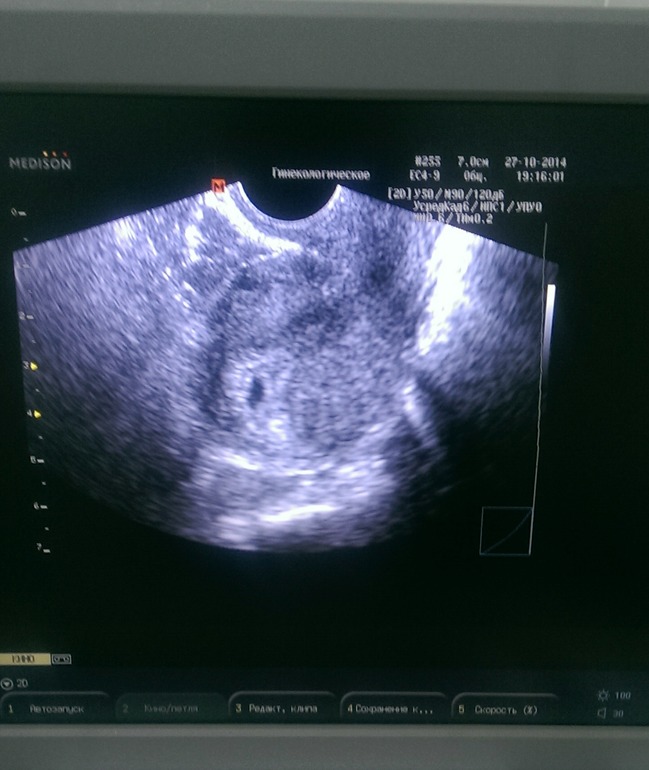

вот она, первая фотография нашего малыша)

Потом было УЗИ в 6 недель - слушали сердечко, в 8 я встала на учет, в 9 недель сделала еще раз УЗИ, ну и в 12 как положено 1-ый скрининг)) У нас конечно есть некоторые проблемы, но я пообещала себе, что обязательно вынесу все что угодно, лишь бы сохранить эту беременность!